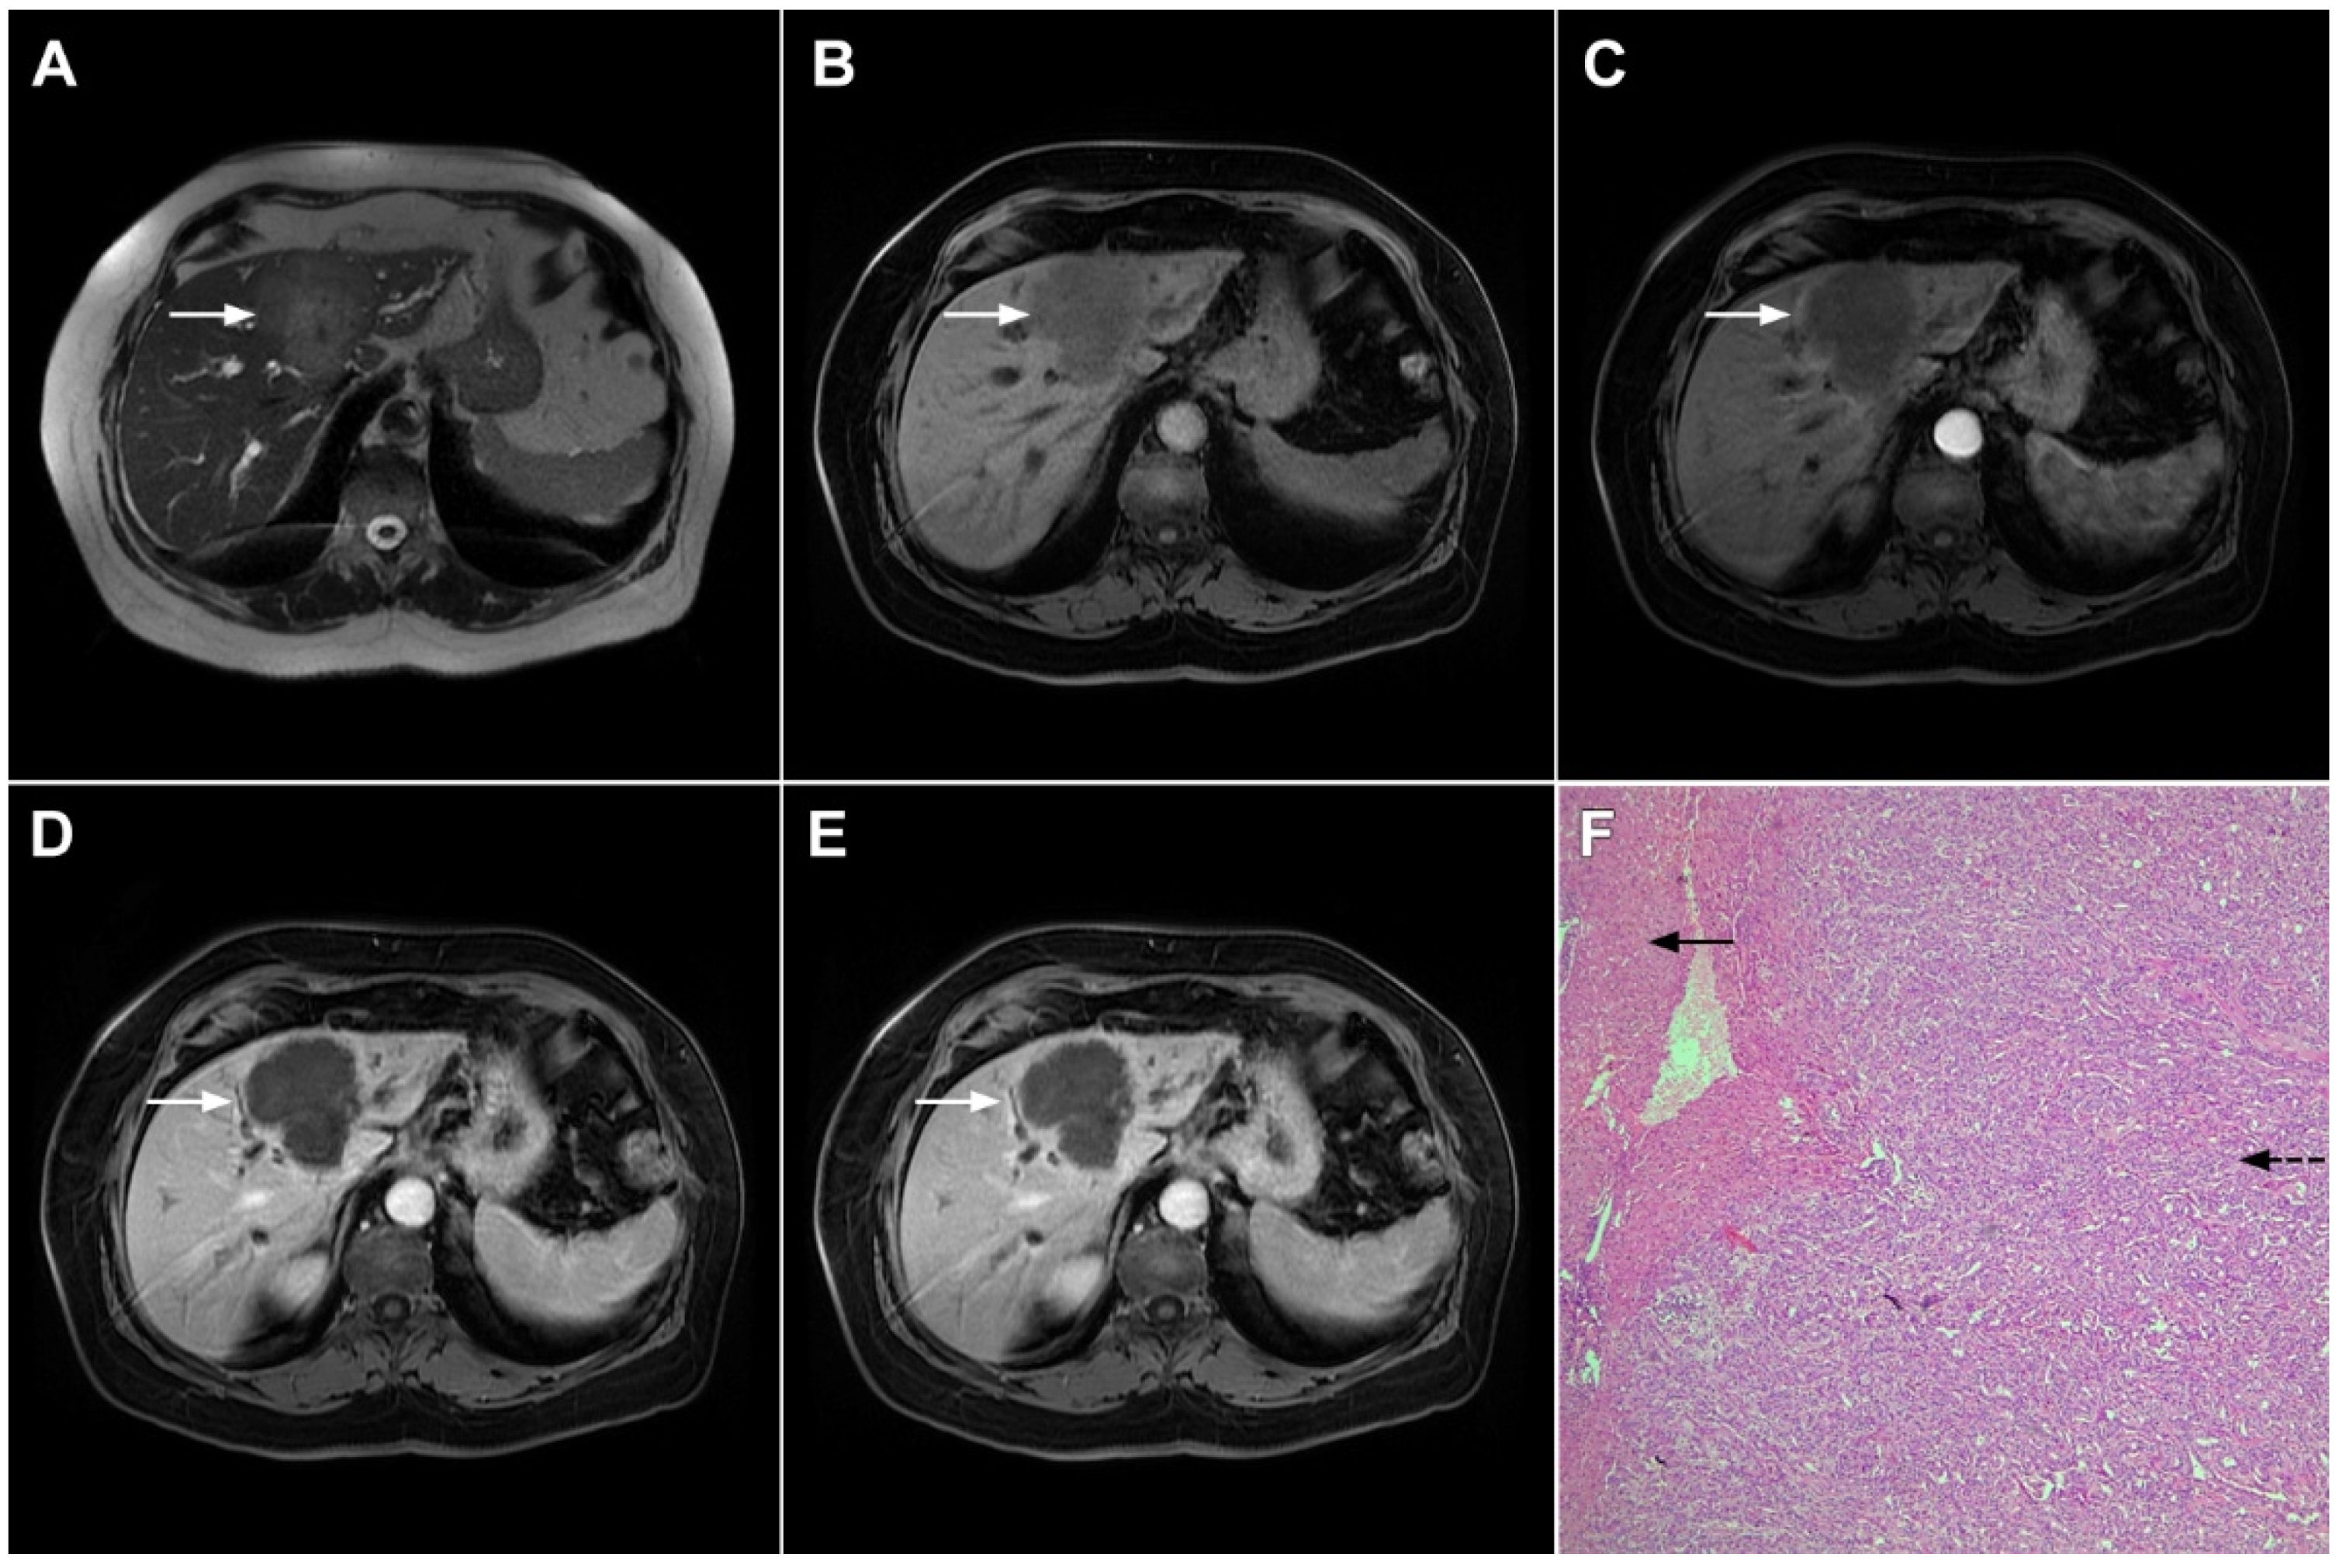

Figure 3.

Mass-forming intrahepatic cholangiocarcinoma in the left liver lobe of a 76-year-old man. Axial T2-weighted FS image shows lobulated hetrogeneously hyperintense hepatic tumor (arrow) with perilesional biliary dilatation (A). Axial diffusion-weighted image (b = 800 s/mm2) shows target-like appearance (arrow) of the lesion that consists of a central darker area and a peripheral hyperintense area (B). Corresponding ADC map is shown on (C).

If hepatocyte-selective contrast media are used, mICC presents typically as hypointense lesions on the hepatobiliary phase due to the lack of functional hepatocytes with a sharp margin between the tumor and the background liver parenchyma [7]. Thus, tumor size as well as the presence of perilesional satellite nodules, could be more precisely evaluated in the hepatobiliary phase in comparison to the MRI with conventional extracellular contrast [18,19]. Additionally, the “cloud sign”, seen as a relatively high cloud-like signal intensity in the central part of the lesion surrounded by a hypointense peripheral rim, is considered characteristic of mICC (Figure 4) [19]. The appearance of mICC in the hepatobiliary phase may be used as a prognostic factor since it correlates well with the content of intralesional fibrous stroma [20]. Namely, if cloud sign is seen it indicates a large amount of fibrous stroma in the central parts of the tumor, which is frequently associated with poor prognosis [20]. Additional imaging features, which are shown to be prognostic factors and can be assessed in the hepatobiliary phase, include capsule penetration and hepatic vein obstruction, as was demonstrated in the study by Kim S et al. [21].

Figure 4.

Mass-forming intrahepatic cholangiocarcinoma in a 68-year-old woman. Axial T1-weighted image after gadoxetic acid administration obtained in arterial phase (A) shows peripherally enhancing lesion (arrow). Portal venous phase in the same patient (B) shows progressive centripetal enhancement of the lesion (arrow) with cloud-like appearance in the hepatobiliary phase (C) consisting of an area of central enhancement and a thin, peripheral, hypointense rim.

Ancillary MRI findings that are frequently seen in mICC include peripheral biliary dilatation, capsular retraction, vascular encasement, lobar atrophy, satellite nodules, and lymphadenopathy [15,16]. Nevertheless, it should be kept in mind that in the parenchymal type of mICC, due to its origin from the small bile ducts, ancillary features such as biliary dilatation, vascular encasement, and lobar atrophy may be absent (Figure 5). In such cases, the presence of typical postcontrast behavior and capsular retraction indicate mICC. On the other hand, some degree of obstruction and peripheral bile duct dilatation is always seen in the ductal type of mICC [15].

Figure 5.

Parenchymal mass-forming cholangiocarcinoma in a 36-year-old man. The lobular slightly hyperintense lesion (arrow) is seen in the liver segment IVA in a T2-weighted image (A) with subtle capsular retraction (dashed arrow). On a plain T1-weighted image (B), the tumor (arrow) is hypointense with irregular discrete peripheral and central enhancements in the arterial phase (C), mild progressive enhancement in the portal venous phase (D), and high signal intensity in DWI (E). Hematoxylin and eosin (H&E) staining (F) showed cholangiocarcinoma (arrowhead) with poorly differentiated components (dashed arrow). Normal liver parenchyma is also shown (arrow); original magnification ×40.